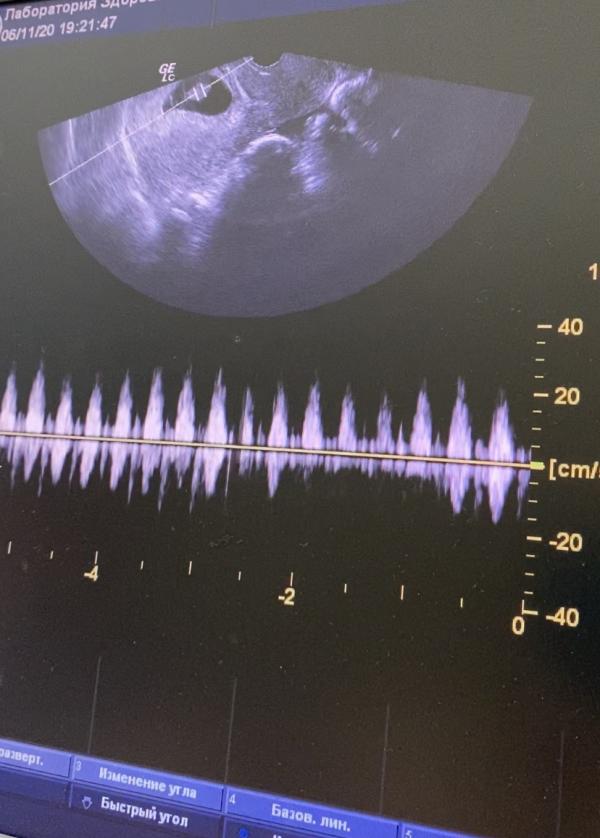

Всё отлично 💚 гематомы уже нет почти, растёт крошка